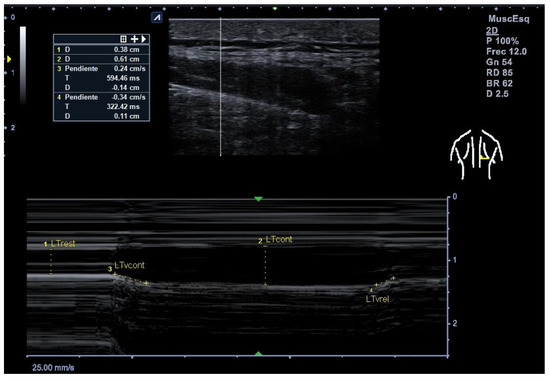

2.8. Thickness Measurements, Velocity of Contraction and Relaxation (M-Mode)

Figure 1. Example of M-mode ultrasound measurement of the lower trapezius muscle. LTrest = lower trapezius thickness at rest (cm); LTcont = lower trapezius thickness at contraction (cm); LTvcont = contraction velocity (cm/s); LTvrel = relaxation velocity (cm/s). The vertical and oblique dotted lines indicate the points used for thickness and velocity calculations. Scale: 25 mm/s (horizontal), 1 cm (vertical).